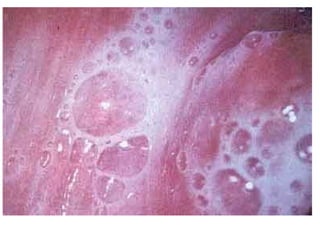

Tricomoníase

Tricomoníase:

O agente etiológico: Trichomonas vaginalis

Transmissão sexual (DST):

Sintomático em mulheres e assintomático em

homens (normalmente é o transmissor)

• Atinge geralmente mulheres adultas

• Transmissão pode ocorrer por objetos e

roupas

• O Trichomonas vaginalis (protozoário).

• Não possui a forma cística, apenas a trofozoítica.

O ( 10 a 30 mm).

• PATOLOGIA

• O homem e assintomático.

• A mulher sintomática:

•

• Secreção vaginal mucopurulenta

• Vaginite caracterizada por corrimento vaginal ,

amarelo - esverdeado, com odor fétido.

• Dor no ato sexual.